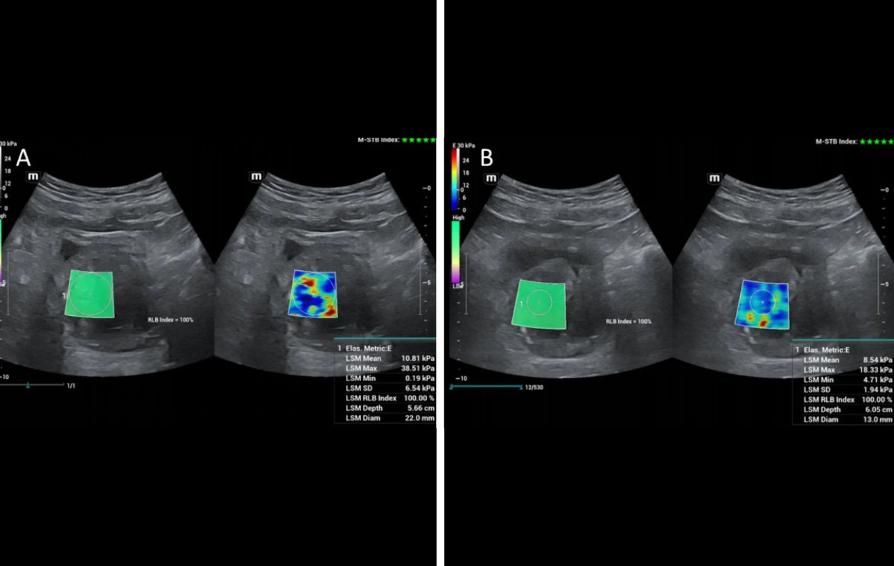

Shear-Wave Elastography for Quantifying Therapeutic Changes in Prostate Elasticity Post-PAE

Shear-wave elastography has also been applied for the study of the prostate before and after PAE and remarkable changes in shear-wave velocity and in the elastic modulus have been recorded; US elastography can therefore detect and quantify therapeutic changes in elasticity of prostate tissue post PAE [6,7]. The respective studies have been performed with transrectal ultrasound [6,7, 8]; however initial experience at the institution of the authors indicates that, with appropriate equipment, transabdominal shear wave elastography of the prostate could also detect changes in prostate elasticity post PAE (Fig 3). This and other research purposes are served by a high-end machine (Resona I9, Mindray) with a wide variety of probes.